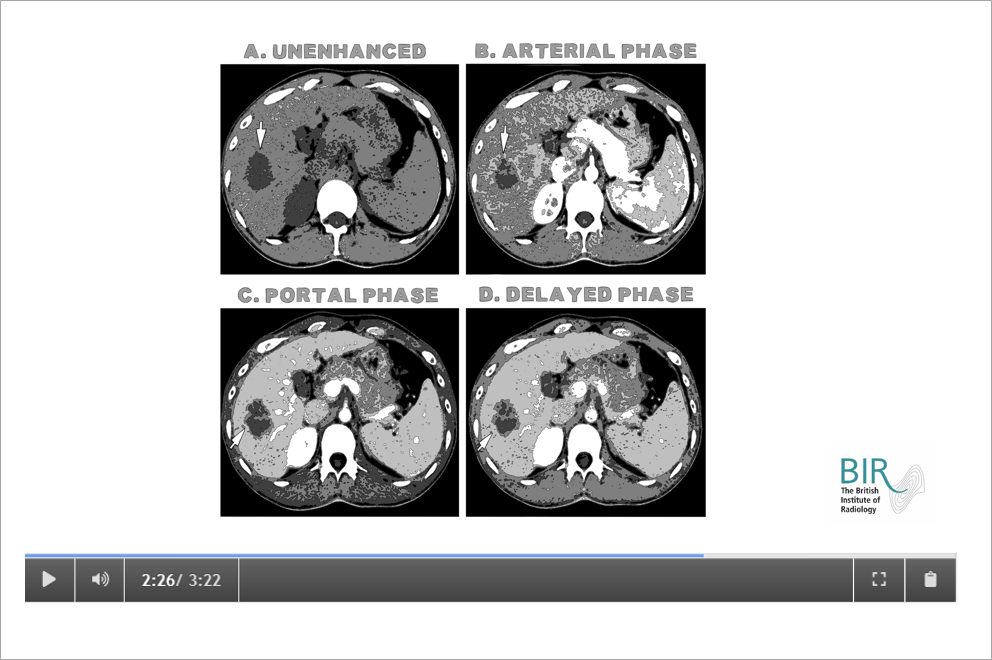

See an example video clip here: